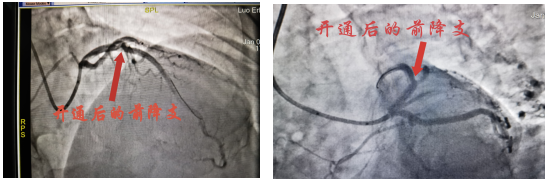

1月4日15:45左右,罗大爷再次出现胸痛,予以“硝酸甘油”舌下含服后无明显缓解,16:00复查心电图,考虑急性前壁ST段抬高型心肌梗塞超急性期,值班医生蔡波副主任医师查看患者后,建议立即行急诊冠状动脉造影及必要时支架植入术,尽早手术才能拯救更多的心肌,患者家属商议后同意并签署心导管诊疗同意书。

术后,罗大爷胸痛明显缓解,在医护人员护送下返回病房继续治疗并密切观察有无并发症等表现。